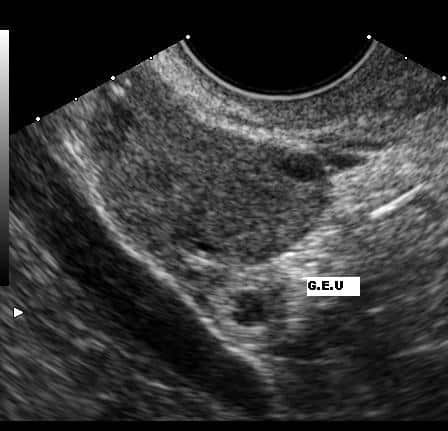

GROSSESSE EXTRA-UTERINE (GEU)

C’est une grossesse qui se développe en dehors de la cavité utérine. Elle succède à une mauvaise implantation de l’œuf et est donc provoquée par une anomalie de la migration et de la nidation.

- Le plus souvent, l’œuf, trop gros, n’a pas pu parcourir la trompe; il s’est arrêté trop t.t et s’est implanté dans la trompe.

- D’autres fois, c’est la captation de l’ovule par le pavillon tubaire qui s’est mal faite. Le spermatozoïde a rejoint l’ovule alors que celui-ci n’était pas dans la trompe. L’implantation se fait alors soit sur place (ovaire, cavité péritonéale), soit dans la trompe.

SYMPTÔMES :

- Des saignements irréguliers : ce sont des pertes de sang noirâtres, brunâtres (couleur sépia) peu importantes

- Pale, livide, agitée, assoiffée = état de choc

- Le pouls est rapide et la tension artérielle est basse.

- Parfois, les douleurs pelviennes sont intenses « ventre de bois »

- Irradiant à l’épaule, itératives*, avec des épisodes successifs de collapsus*.

Quand le diagnostic de grossesse extra-utérine est évoqué, la patiente doit toujours être hospitalisée en urgence, risque d’une rupture de la trompe utérine entraînant une hémorragie interne grave.

RISQUE :

- La complication d’une grossesse extra-utérine est une rupture de la trompe utérine entraînant une hémorragie interne grave.

SOINS :

- Installer la passagère tête basse

- Jambes surélevées

- Mettre vessie de glace sur l’abdomen

- Oxygène

- Surveiller les constantes

- Déroutement Urgence

Attitude à avoir : installer le PAX tête basse, jambes surélevées, mettre une vessie de glace sur l’abdomen, donner de l’O2 et surveiller ses constantes. Envisager un déroutement. La douleur est violente, brutale. Ne pas donner à boire.